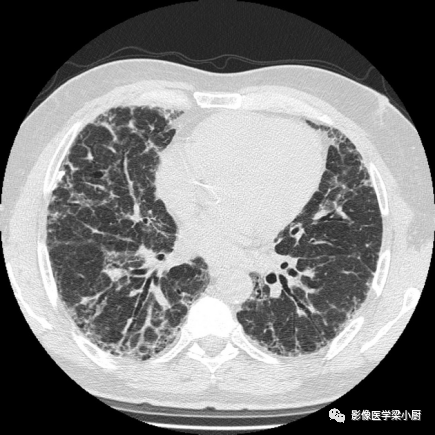

分布的不均匀性:HRCT肺外周部位和胸膜下区不均匀分布,正常肺组织和病变区(网格、牵拉性支气管扩张或蜂窝)交替。病变常呈双侧不对称分布。

IPF患者牵拉性支扩